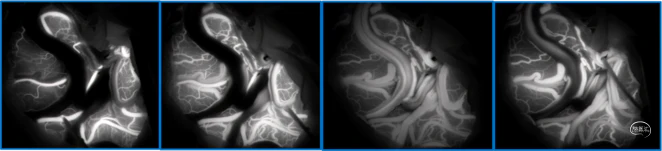

典型病例

![]()

![]()

蝶顶窦旁DAVF属于Borden III型,需要积极外科治疗。

蝶顶窦旁DAVF,可吸引前和中颅窝硬膜的所有动脉参与供血。其中颈内动脉及其分支的供血可以使用显微外科技术阻断;颈外动脉的供血动脉可以使用介入栓塞技术阻断。

介入栓塞眼动脉供血的要点:超选左侧眼动脉,跃过视网膜中央动脉,栓塞脑膜回返动脉对DAVF的供血。目的:保护眼动脉视网膜中央动脉分支,避免后期栓塞颈外动脉的供血动脉时损伤眼动脉。

引流静脉是否引流进入海绵窦,决定DAVF诊断为“颈动脉-海绵窦动静脉瘘”还是“蝶顶窦旁DAVF”。

静脉的引流路径决定患者静脉高压的临床表现,预后风险,治疗方案。

稳妥的外科治疗方案:先介入栓塞颈外动脉的供血动脉,然后显微手术切断颈内动脉的供血动脉,阻断引流静脉,电凝封闭硬膜瘘口。